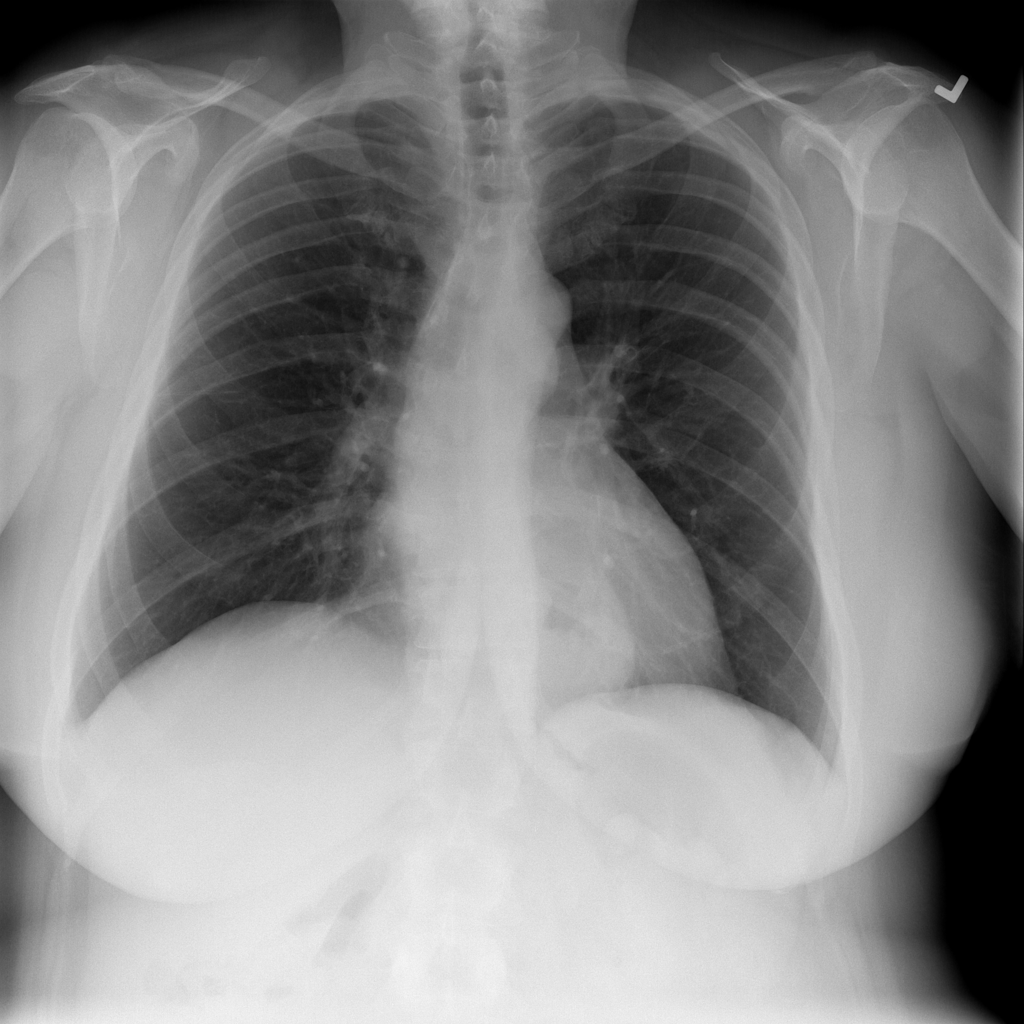

PAT-C048 · IMG-000Hernia

PAT-C048 · IMG-000

PA